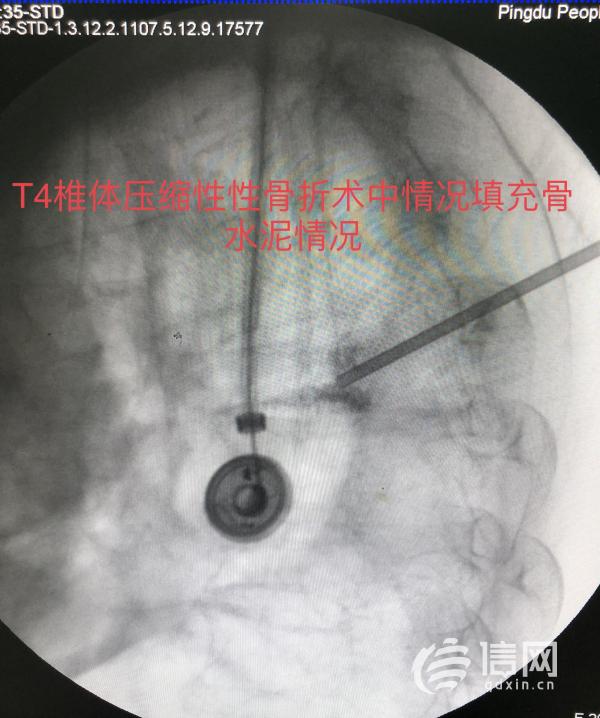

潘雲春副主任醫師建議患者在病情穩定後手術治療,蔡女士及其家人剛開始因高齡老人基礎疾病較多,且聯合損傷存在,老人及家屬對於手術治療比較排斥。潘雲春副主任醫師帶領大家積極討論後決定對蔡女士採用經皮椎骨成形微創手術,儘量減少手術創傷及術後併發症的發生。再次與家人溝通後,得到了家人和蔡女士的理解和支援,局麻下為蔡女士實施了胸4椎體及胸11椎體微創經皮椎骨成形術,手術過程很順利,手術用時60分鐘,基本無出血,刀口3毫米。

據悉,平度市人民醫院已熟練掌握T5及以下椎體的微創手術(PVP或PKP),潘雲春副主任醫師表示蔡女士的T4椎體壓縮性骨折在術前評估時就面臨著嚴峻的挑戰,對T4椎體在C臂透視下實施微創手術在平度市人民醫院尚屬首例,且T4椎體壓縮骨折合併胸骨體骨折有出現遲發性神經功能障礙的可能,無形中增加了手術的難度,對手術醫師精準的定位,穿刺的力度的大小及角度提出了更高的要求。